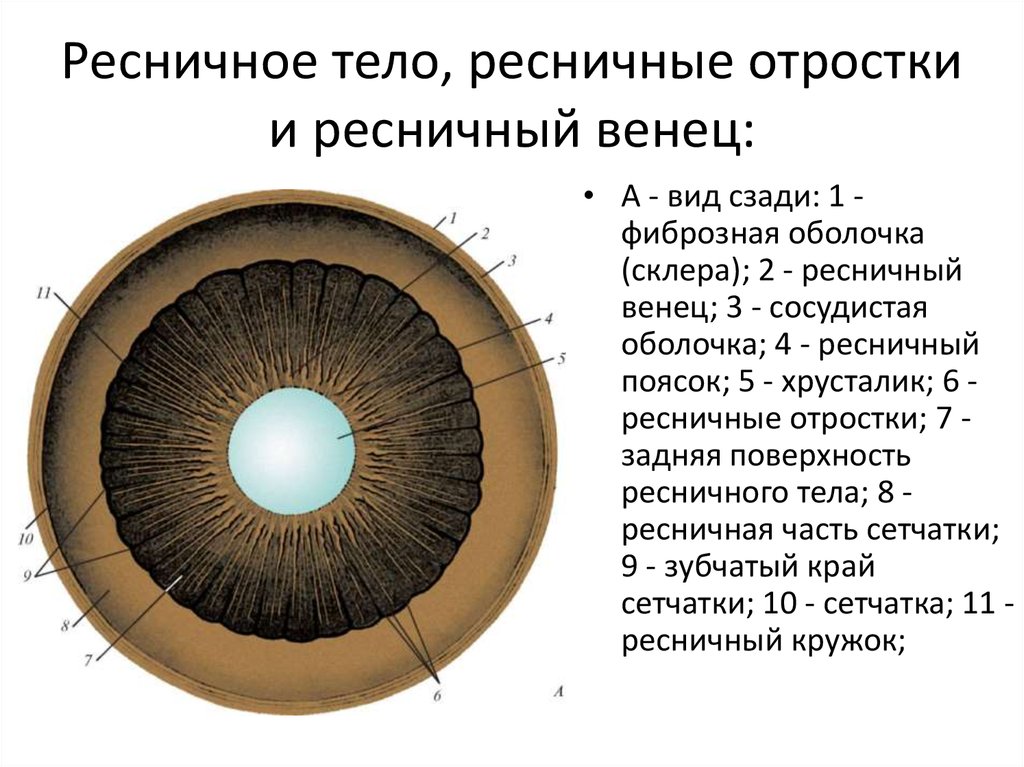

КТ-графики и изображение строения глаза